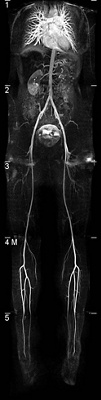

Abbildung des arteriellen Gefässbaums mittels MR-Angiographie.

Abbildung des arteriellen Gefässbaums mittels MR-Angiographie. © Interventionelle Radiologie - Swiss Intervention

MR-Angiographie

Unter anderem stützen wir uns im Rahmen der Bilddiagnostik bei dieser Verdachtsdiagnose auch auf die MR-Angiographie.